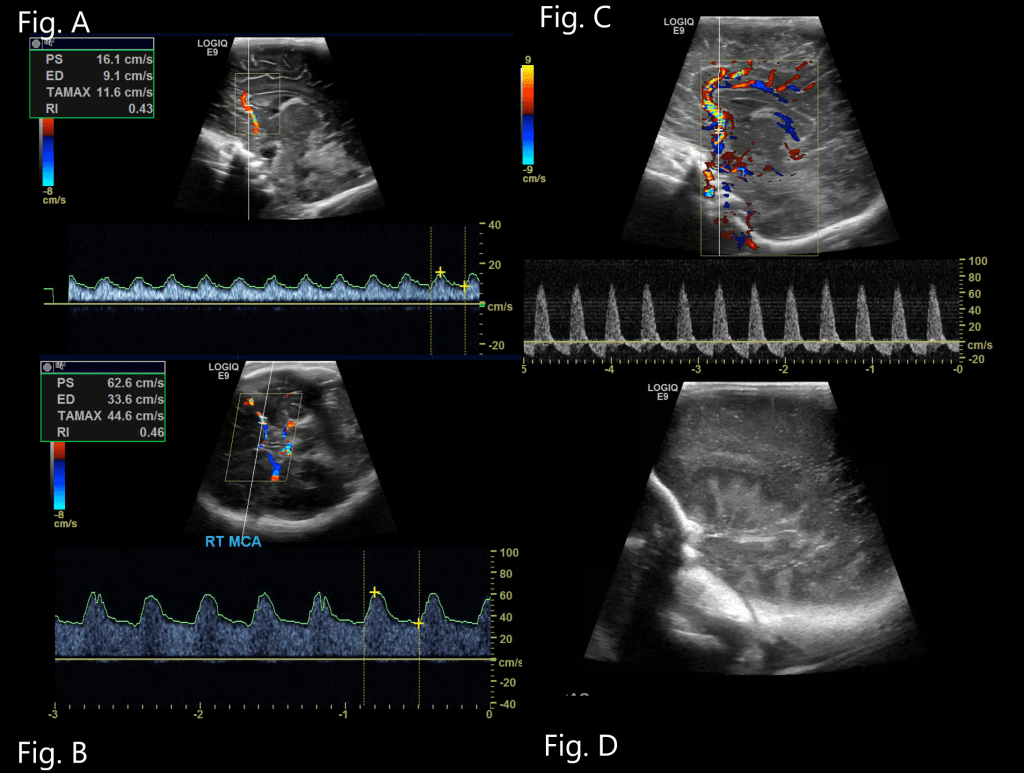

Resistive Index

Resistive index of the middle cerebral arteries, Loss of cerebral autoregulation in HIE can predispose to reduced/absent diastolic blood flow in cerebral arteries leading to increased RI (>0.80) or elevated diastolic flow due to arterial vasodilation resulting in reduced RI. Decreased RI has been well documented in asphyxia and found to increase the risk of death or cerebral palsy by 23.4 times.